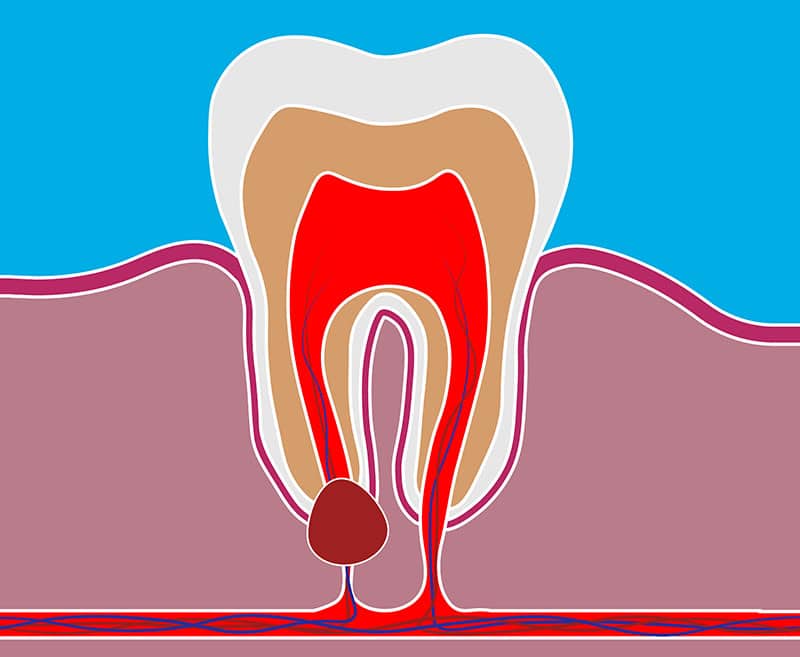

Пульпит это наиболее запущенная форма кариеса воспаление нерва зуба, которое возникает в результате попадания в корень зуба каких-либо микробов (во время лечения, травмы зуба или запущенном варианте кариеса). Проводится следующее лечение зубов - как правило, удаляется нерв, проводится лечение всех каналов зуба, после чего каналы зуба пломбируются и зуб реставрируется пломбой или коронкой. Удаление нерва, благодаря современной анестезии, совершенно безболезненно. Симптомы пульпита: сильная зубная боль (постоянная или прерывистая), возникающая в ночное время, реакция зуба на горячее.

Образуется она, как правило, у корня зуба, ее рост может приводить к уменьшению здоровой ткани вокруг корня зуба, в результате чего зуб может утратить свою устойчивость и выпасть. Кисту зуба необходимо лечить, а в случае безуспешного лечения - удалять, чтобы предотвратить ее развитие (как правило, хирургическим методом). Киста зуба может также привести к развитию гнойных образований в костной ткани (периоститу). Симптомы кисты зуба: чувствительность зуба при жевании, на надавливание. Пока киста зуба небольших размеров, она никак себя не проявляет, однако при достижении размеров в 3-4 см в диаметре, обнаружить кисту можно за счет видимого отека лица и температуры.